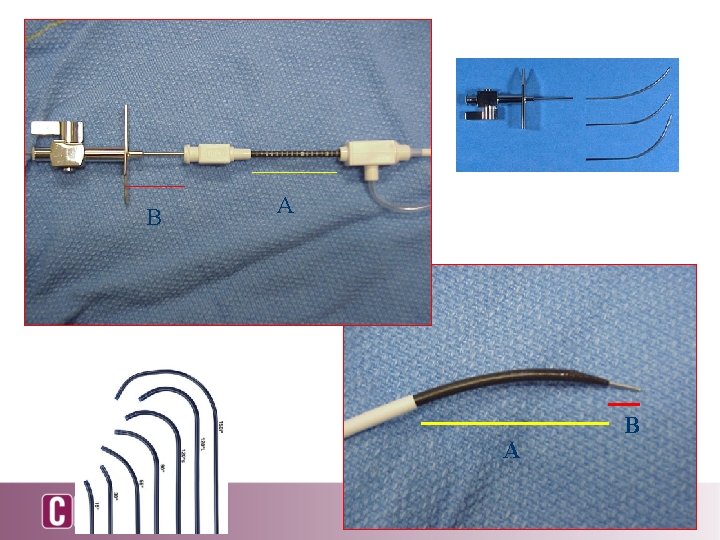

B A A B